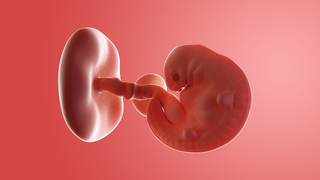

What does my baby look like?

Your baby, or embryo, is around 2mm long (about the size of a sesame seed).

The face is starting to take shape, with a tiny nose and little eyes, which stay closed until around 28 weeks. Your baby's brain and spinal cord are forming rapidly inside you.

Your baby already has some of its own blood vessels and a string of them will make up the umbilical cord. This cord delivers everything it needs from the placenta.

The placenta, which is being created now, will give your baby nutrients and oxygen, while removing waste products.